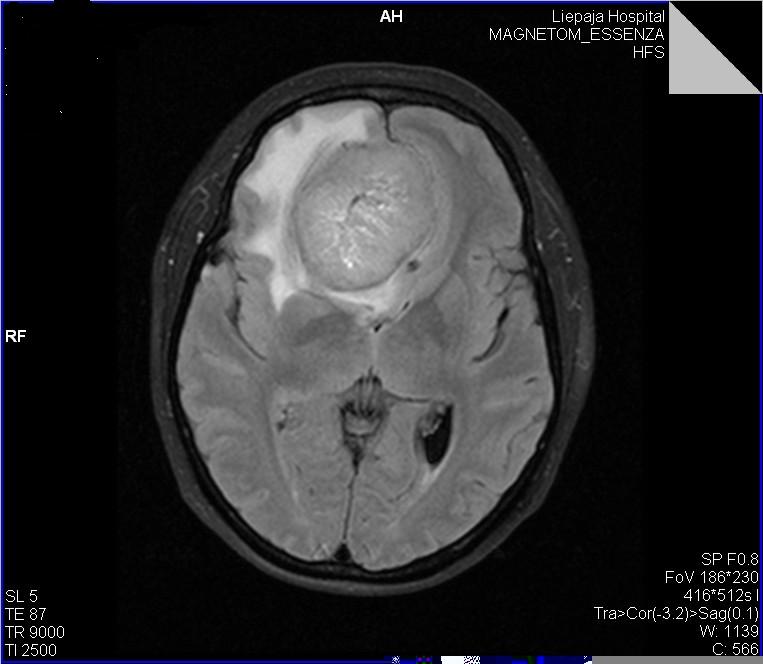

- Компьютерную томографию (КТ) — точность результата составляет 90%;

- Магнитно-резонансную томографию (МРТ) – с точностью 85%;

Каждый из типов томографии необходим для получения полной картины состояния опухоли:

- МРТ – определяет наличие новообразования;

- КТ – определяет задействованность костной ткани и опухолевых кальцинатов;

- ПЭТ – определяет степень рецидива опухоли, т.е. распространения на другие части организма.